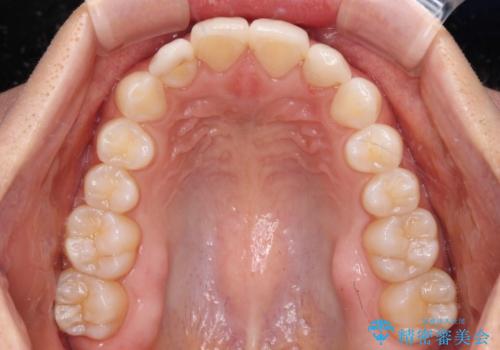

- 大きすぎる上顎前歯と、隙間の空いた下顎歯列を気にして来院された患者様です。

上顎前歯にはセラミッククラウンが装着されており、顔や他の歯と比較して幅の大きい状態でした。

下顎前歯は空隙歯列弓であったので、アンカースクリューとワイヤー装置を用いてスペースを閉じていくこととし、上顎前歯は矯正治療用の仮歯に置き換えた上で、仮歯の大きさを削って小さくしながら、上下前歯部の部分矯正を行うこととしました。